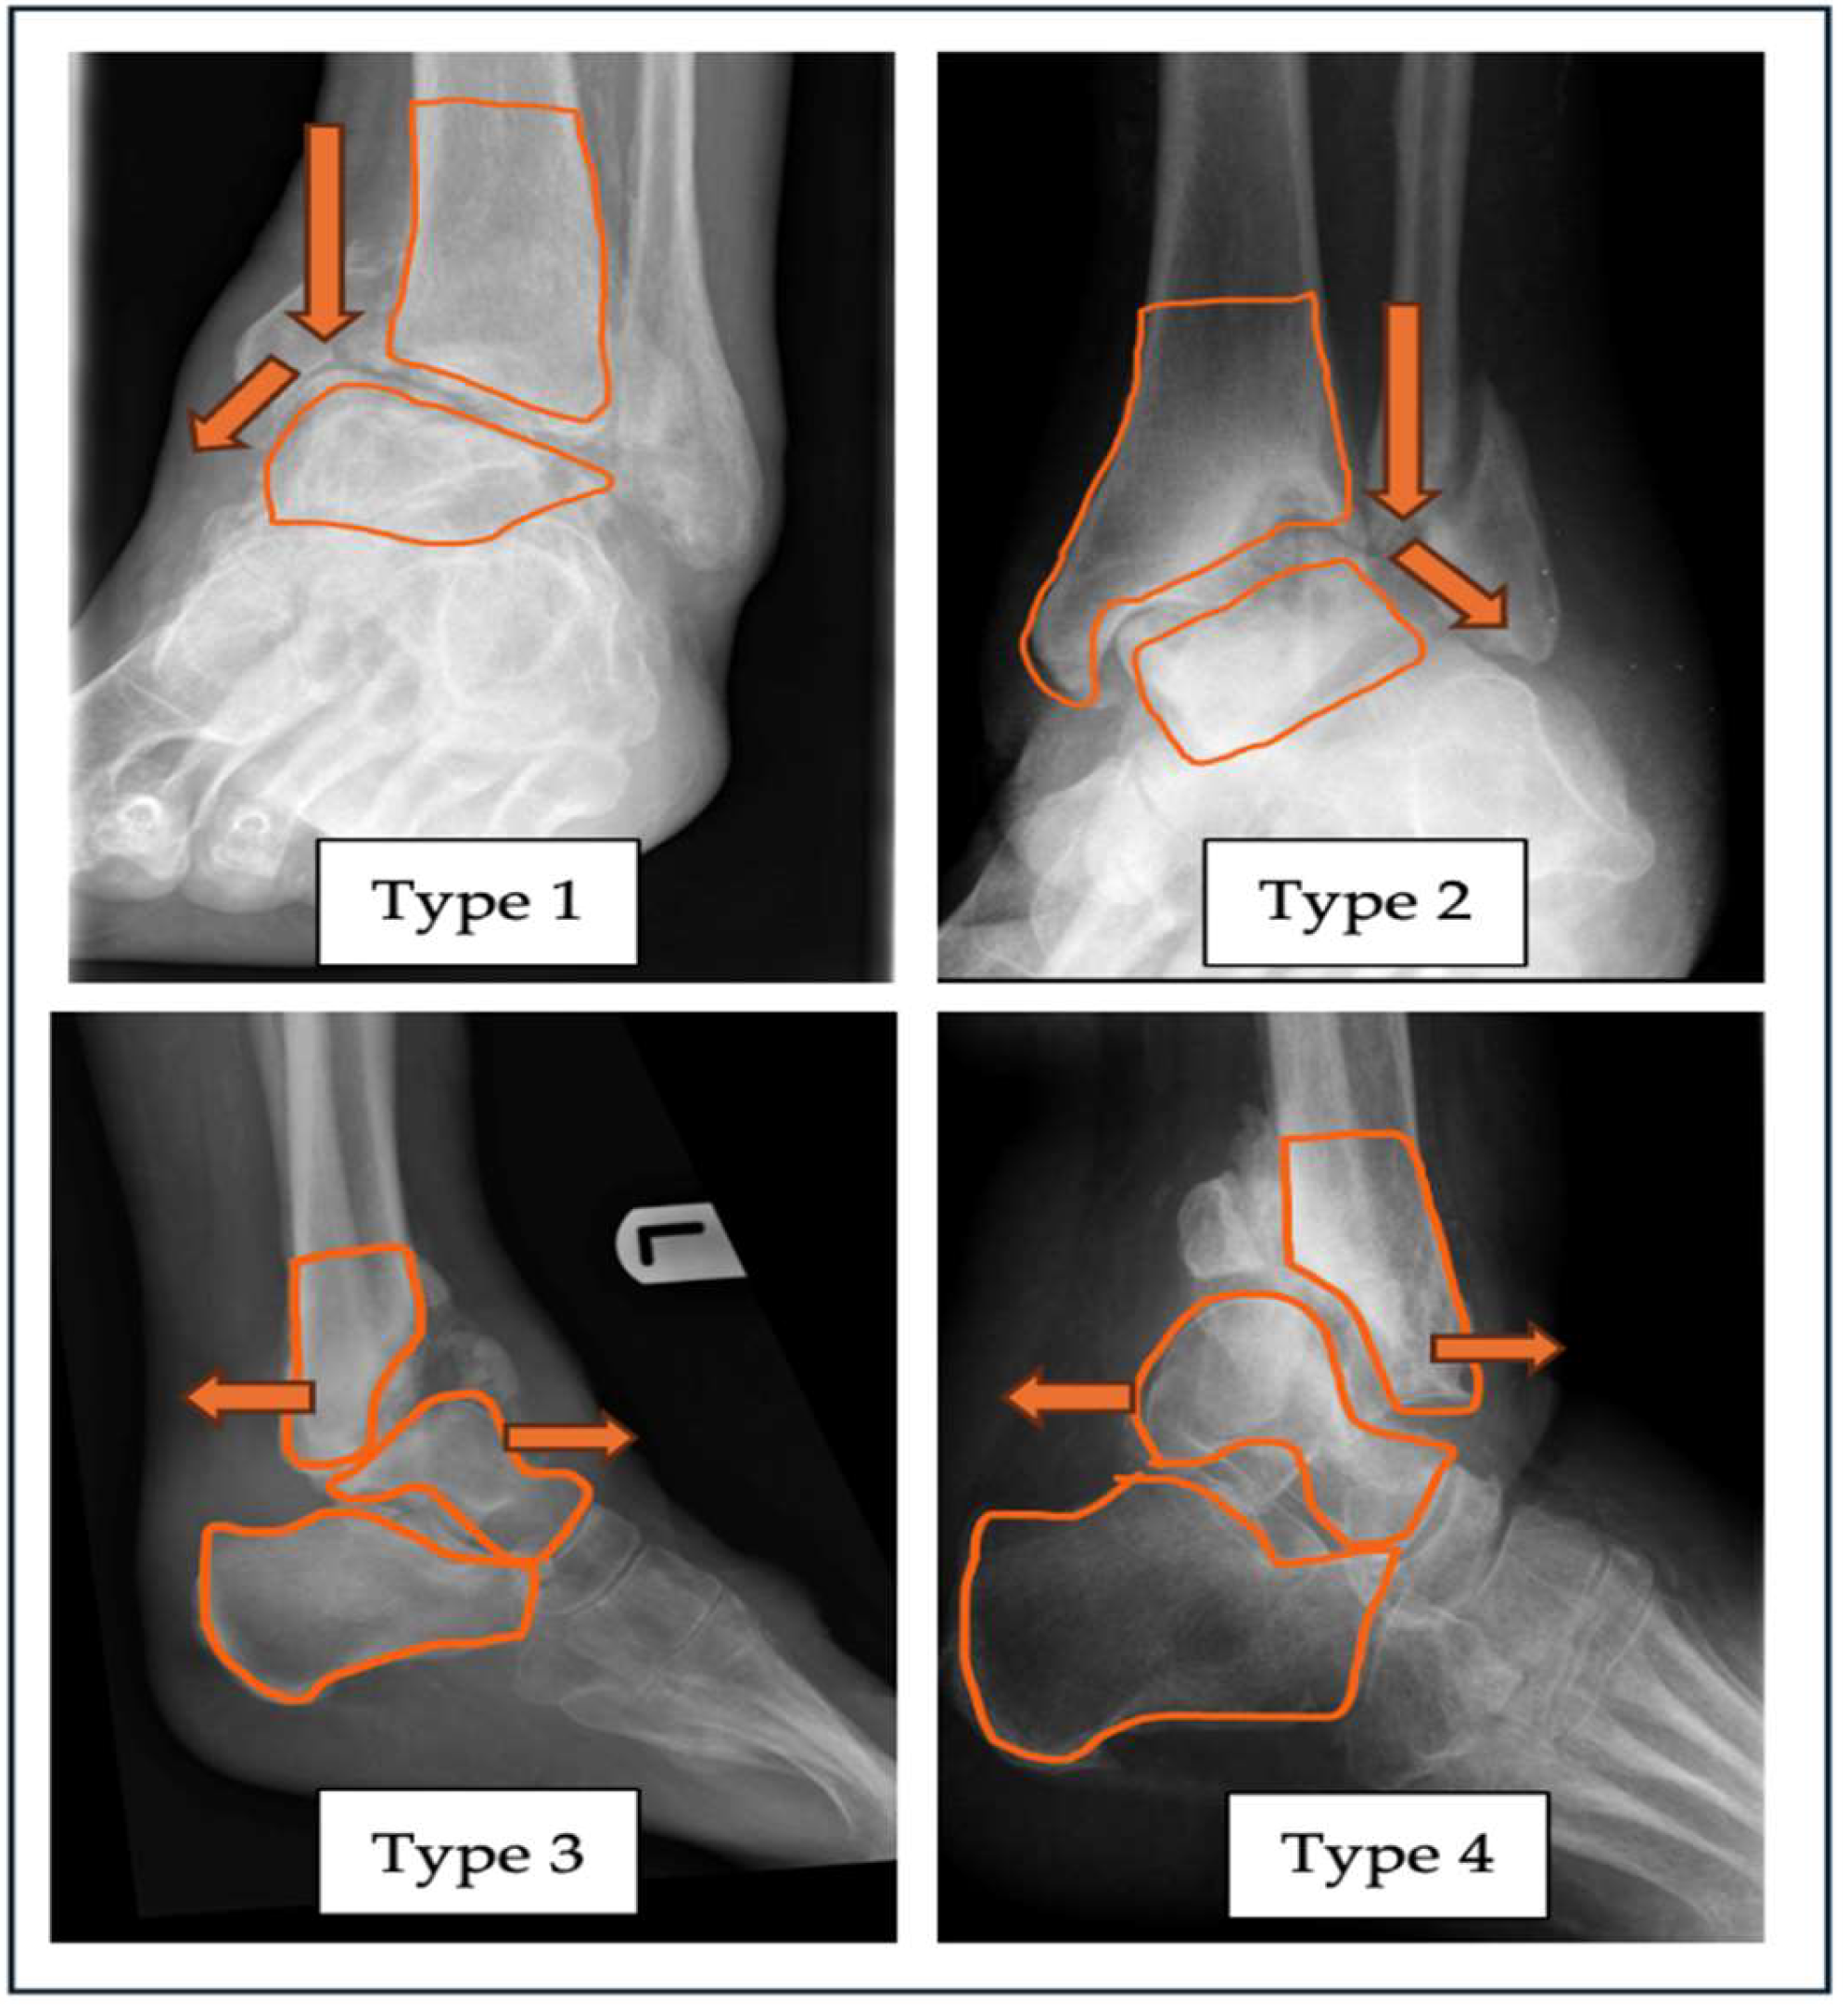

| “A” - Alignment | Varus (Type 1) |

Valgus (Type 2) |

Anterior (Type 3) |

Posterior (Type 4) |

| Neutral – label as Type N Combined Label as Type 5 |